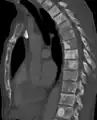

| Sclerosis of the bones of the pelvis due to prostate cancer metastases | |

Osteosclerosis is a disorder that is characterized by abnormal hardening of bone and an elevation in bone density. It may predominantly affect the medullary portion and/or cortex of bone. Plain radiographs are a valuable tool for detecting and classifying osteosclerotic disorders.[1][2] It can manifest in localized or generalized osteosclerosis. Localized osteosclerosis can be caused by Legg–Calvé–Perthes disease, sickle-cell disease and osteoarthritis among others. Osteosclerosis can be classified in accordance with the causative factor into acquired and hereditary.[2][1]

Osteosclerosis can be detected with a simple radiography. There are white portions of the bone which appear due to the increased number of bone trabeculae.